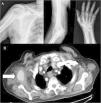

A male aged 83, receiving atrial fibrillation anticoagulation therapy with rivaxoaban, presented at the emergency department due to persistent pain his right shoulder which had spread to the back of his upper arm, forearm and wrist, of 10-day onset after an injury to the upper right limb in forced abduction. On examination a small throbbing axillary haematoma was observed, a strength of 1/5 on extending the fingers and of 3/5 on extending the wrist, hypesthesia in anatomical snuff box and first finger. Radial pulses were present and symmetrical. Requested X-rays showed no fractures or dislocations (Fig. 1a).

On suspicion of brachial plexus compromise cervical magnetic resonance imaging (MR) was requested, which resulted normal, together with electromyography which showed partial axonotmesis of the radial nerve. CT of the chest was also performed which showed an oval mass in the right armpit with irregular edges and a density similar to the axillary artery. As a result an angiography CTG scan was performed (Fig. 1b) which confirmed the said image was a continuity and pseudoaneurysm of the right axillary artery, axillary haematoma and axonotmesis of the ipsilateral radial nerve secondary to blunt trauma was diagnosed. The patient was referred for vascular surgery where a Doppler ultrasound scan was performed, draining of the haematoma and exclusion of the pseudoaneurysm through a stent. The patient is currently in physiotherapy treatment to recover strength lost from the injury and periodically goes to the outpatient rheumatology and vascular surgery department for check-ups.